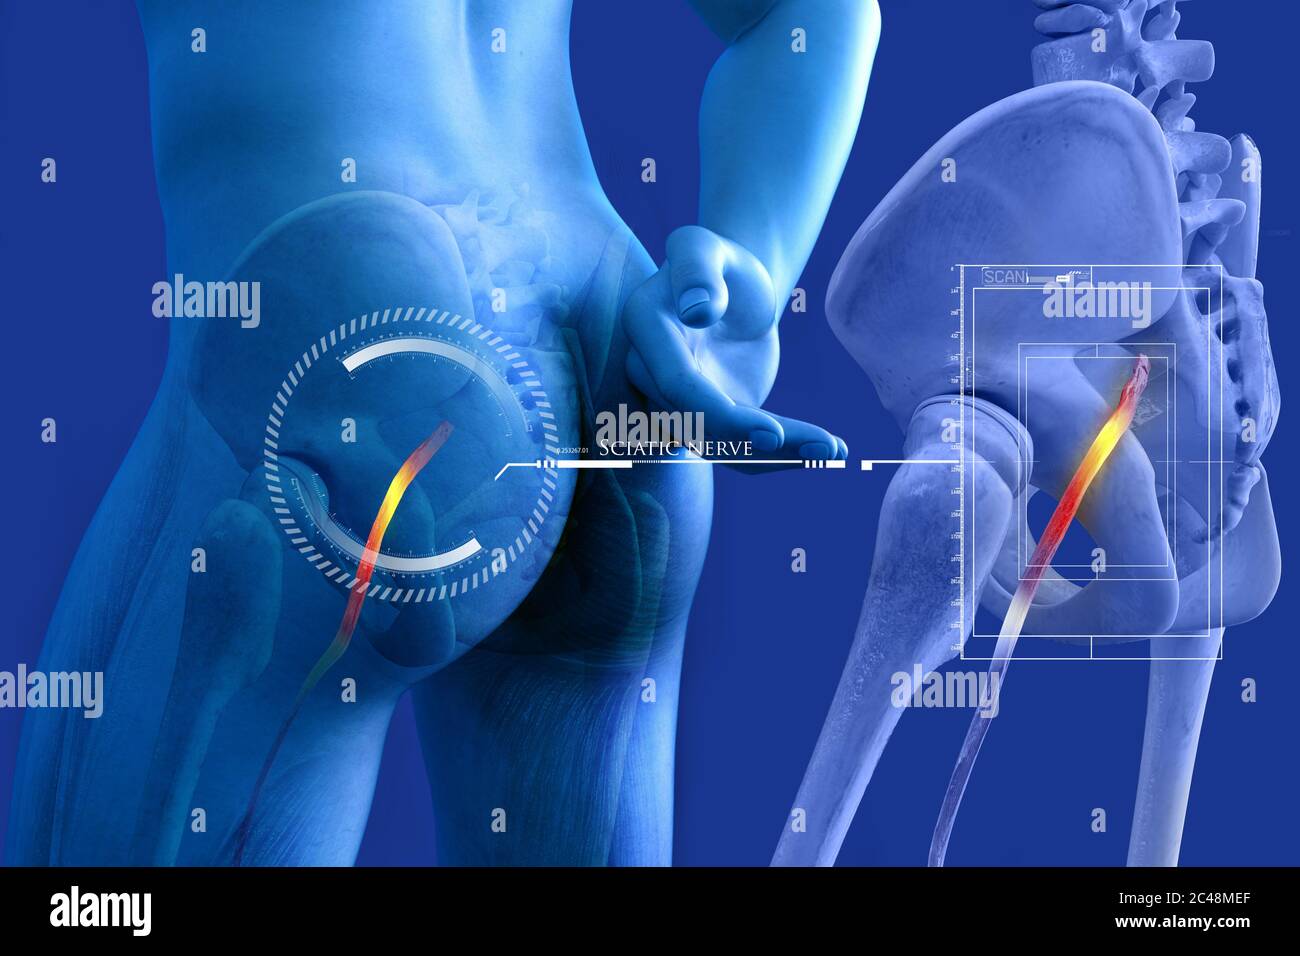

Nerf sciatique humain pincé, vision anatomique. illustration 3d. Banque D'Imageshttps://www.alamyimages.fr/image-license-details/?v=1https://www.alamyimages.fr/nerf-sciatique-humain-pince-vision-anatomique-illustration-3d-image364068055.html

Nerf sciatique humain pincé, vision anatomique. illustration 3d. Banque D'Imageshttps://www.alamyimages.fr/image-license-details/?v=1https://www.alamyimages.fr/nerf-sciatique-humain-pince-vision-anatomique-illustration-3d-image364068055.htmlRF2C48MEF–Nerf sciatique humain pincé, vision anatomique. illustration 3d.